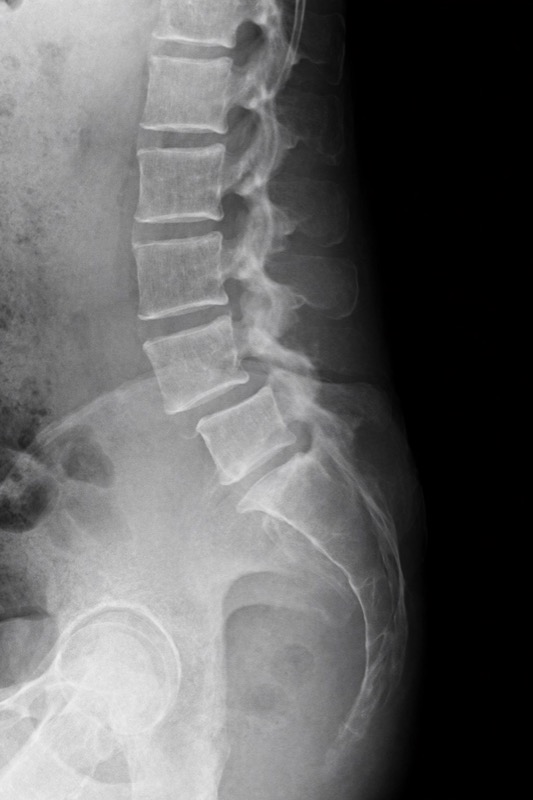

La espondilolistesis es una condición en la que una vértebra se desliza hacia adelante sobre la vértebra que está debajo de ella. Este desplazamiento es más común en la región lumbar, especialmente entre L5 y S1.

El grado de deslizamiento se clasifica del I al V, siendo el grado I un desplazamiento mínimo y el grado V el más severo.

- Radiografías: Permiten visualizar el desplazamiento vertebral y determinar el grado

- Radiografías dinámicas: En flexión y extensión para evaluar inestabilidad